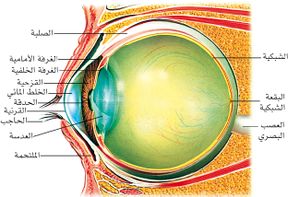

نزف داخل العين Vitreous hemorrhage هو تسرب الدم من الجسم الزجاجي، أو القزحية، أو تحت الملتحمة في العين.

الجسم الزجاجي كتلة هلامية شفافة تملأ كرة العين لا أوعية دموية فيها.

يشغل الزجاجي المسافة الواقعة بين حليمة العصب البصري في الخلف والجسم البلوري (العدسة) في الأمام، ويعطي العين شكلها وقوامها. والجسم الزجاجي لا يفرز ولا يفرغ وضياعه لا يُعّوض ويؤدي إلى ضمور العين، تحيط به محفظة الزجاجي، ويفصله عن الشبكية طبقة المحددة الباطنية الشبكية.

نزف القزحية

القزحية iris هي حجاب صباغي عضلي غني بالأوعية، تؤلف القسم الأمامي من العنبة وتشكل مع القرنية cornée من الأمام الغرفة الأمامية. وهي صفيحة دائرية قطرها 12مم، كتيمة تمنع نفوذ الضوء إلى داخل العين إلا من ثقب في مركزها هو الحدقة pupille التي تتسع وتتقبض لتحدد كمية الضوء التي تدخل العين.